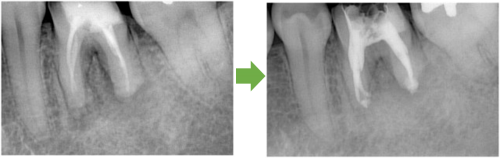

かぶせ物と土台を外します→根の管に詰まっている薬を外します→再び根の管を拡げます

根の管を拡げ終えました→症状がなくなりました→最終的なお薬を詰めます